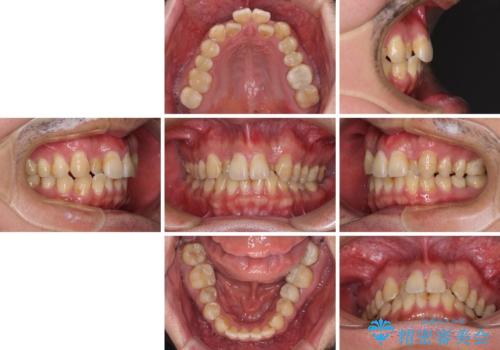

- 虫歯が多く、セラミッククラウンにより虫歯治療を行っている途中で矯正治療をしたいとのことで来院された患者様です。

上顎前歯が舌側に転位しており、なるべく早く楽に矯正したいとのことで、ワイヤー矯正を行うこととしました。

虫歯治療途中の歯は仮歯が装着されていたため、そのまま矯正治療を行い、矯正後に補綴治療を行うこととしました。